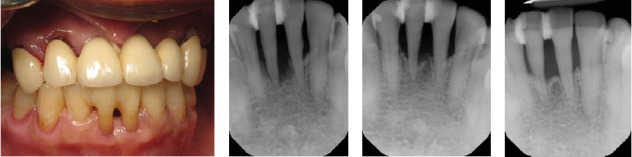

目的:牙周夹板为稳定活动牙提供了一种无创、廉价的治疗方法。本研究评估牙周夹板的使用寿命和长期稳定性。方法:对上颌前牙或下颌前牙接受夹板的患者进行回顾性分析。收集的数据包括患者的年龄、性别、夹板放置的指征、放置的日期、所涉及的牙齿、骨质流失的百分比、桥桥的存在以及加固的类型。数据用描述性统计进行汇总。采用t检验分析骨质流失的差异。结果:本研究共纳入154例。患者平均年龄为57.2岁,年龄范围从17岁到93岁,男性和女性的比例几乎相等(54%对46%)。手术从2003年进行到2024年。大多数是下颌夹板(20%)或没有桥架(47%)。上颌夹板占33%的样本(12%有桥式,21%没有)。68% (n = 105)的病例的夹板是牙周的。创伤占18%,包括口腔穿孔和撕脱。在有资料的情况下,评估牙周病例的骨质流失情况。平均损失为76.5%,从30%到100%不等。骨丢失与夹板的位置(p值= 0.3690)、患者性别(p值= 0.3391)或夹板加固的使用(p值= 0.3548)无显著相关性。只有40%的夹板得到了加固。超过一半的病例的寿命为10年或更长(n = 82,55%)。结论:夹板可为活动牙提供长期支持,有助于牙周受损牙的维持。在替换单个前牙时,带桥托的夹板可以提供稳定的临时假体作为临时可移动矫治器的替代方案。

Objective: Periodontal splints offer a noninvasive and inexpensive treatment modality to stabilize mobile teeth. This study evaluated periodontal splints to examine their longevity and long-term stability. Methods: A retrospective chart review was performed for patients who received splints on mandibular or maxillary anterior teeth. Data collected included patient age, gender, indication for splint placement, date of placement, teeth involved, percent bone loss, presence of a pontic, and type of reinforcement. Data were summarized with descriptive statistics. Differences in bone loss were analyzed using t-tests. Results: A total of 154 cases were included in the study. The average patient age was 57.2 and ranged from 17 to 93, with nearly equal rates of males and females (54% vs. 46%). Procedures were performed from 2003 until 2024. The majority were mandibular splints with (20%) or without a pontic (47%). Maxillary splints accounted for 33% of the sample (12% with pontic and 21% without). The nature of the splint was periodontal for 68% (n = 105) of the cases. Trauma accounted for 18% and included incidents with oral piercings and avulsion. Periodontal cases were assessed for bone loss where data were available. The average loss was 76.5% and ranged from 30%to 100%. Bone loss was not significantly associated with the location of the splint (p-value = 0.3690), patient gender (p-value = 0.3391), or use of splint reinforcement (p-value = 0.3548). Only 40% of splints were reinforced. More than half of the cases had a longevity of 10 or more years (n = 82, 55%). Conclusion: Splinting can provide long-term support to mobile teeth and aid in maintaining periodontally compromised teeth. In replacing single anterior teeth, a splint with a pontic can provide a stable provisional prosthesis as an alternative to a temporary removable appliance.